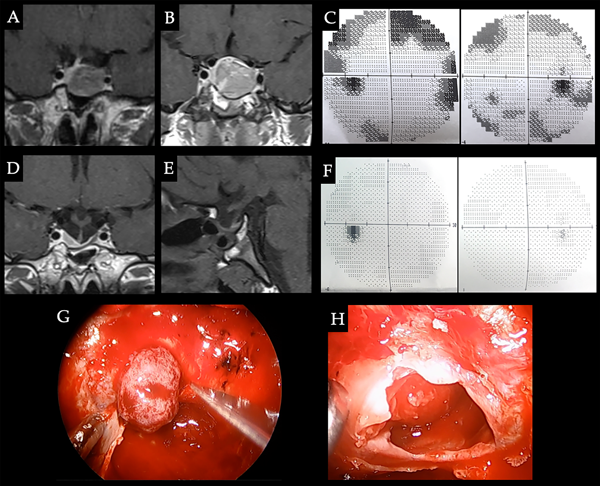

Caso 1. Resistencia a los AD. Paciente femenina de 18 años con antecedente de migraña que consultó por amenorrea secundaria de 2 años de evolución. En el laboratorio presentó PRL 1390 ng/ml, siendo el resto del panel hormonal normal. A. En RM de hipófisis se evidenció una lesión selar compatible con adenoma e inició tratamiento con cabergolina, normalizando los valores de PRL. B. RM de control a 3 meses del tratamiento que evidenció aumento del tamaño tumoral, el cual contacta con la vía óptica. C. CVC que muestra disminución de la sensibilidad periférica, por lo cual se decide conducta quirúrgica. D-E. RM postoperatoria con resección tumoral completa. F. Normalización del campo visual y normalización del nivel de PRL sin medicación. G. Luego de la apertura dural se visualiza adenoma de consistencia blanda aspirable. H. Cavidad postquirúrgica y glándula hipofisaria.